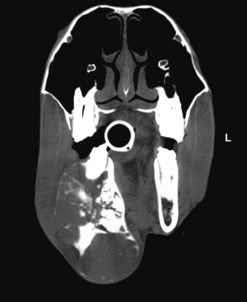

Dorsoventral projection (Figs 13.1213.13)

This view is quite easy to obtain in the sedated horse and is particularly useful for visualizing the ventral conchal sinus, nasal cavities, and nasal septum. Additionally, it can be used for evaluating maxillary/mandibular fractures; bony distortion of the maxilla associated with periapical infection of the rostral cheek teeth or intra-sinus masses. Laterally or medially displaced teeth and fractured maxillary teeth (particularly sagittal fractures) can also be visualized with this view; however, these abnormalities should be apparent during a thorough oral examination. The extremely dense bone of the hemimandibles makes it almost impossible to evaluate normally positioned mandibular cheek teeth using this projection.

An increased exposure is required for this projection compared to those used for lateral or lateral-oblique views of the skull. The X-ray beam is directed perpendicular to the dorsal plane of the head (which runs parallel to the hard palate) with the cassette held parallel with the ventral mandible and positioned as caudally as possible (Fig. 13.12). Because the mandibular cheek teeth rows are so close together (anisognathia), even a small degree of obliquity obscures one nasal cavity, ventral conchal sinus, and maxillary cheek teeth row and prevents accurate comparison of left and right maxillary sinus opacity; therefore, great care must be taken to ensure that the head is absolutely straight and the beam perpendicular to the dorsal plane. The centering point is in the midline of the dorsal aspect of the head at the level of the rostral aspect of the facial crests. Collimation of the primary beam should include the left and right lateral extents of the skull, the caudal aspects of the bony orbits and the diastemata, rostrally (Fig. 13.13).

In the anesthetized horse, ventrodorsal radiographs can be obtained with the horse positioned in dorsal recumbency and the head and neck fully extended. Ideally, the endotracheal tube should be removed to prevent its superimposition on the nasal cavities and conchal sinuses.